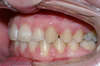

Vues avant le traitement